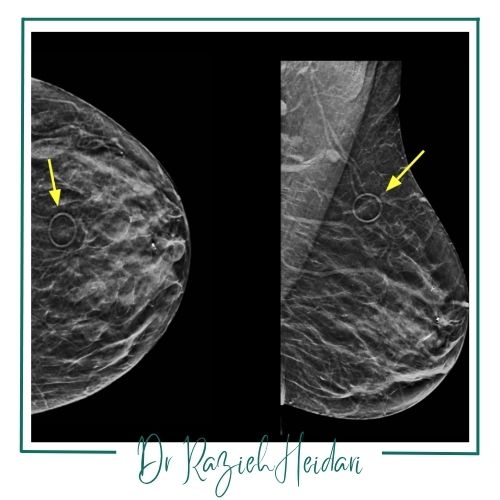

در مرکز ژرفا از تکنولوژیهای نوین و پیشرفته مانند رادیوگرافی دیجیتال و سونوگرافی استفاده میشود که امکان تشخیص دقیق و زودهنگام بیماریها را فراهم میآورد. این تجهیزات پیشرفته بهویژه برای شناسایی بیماریها در مراحل اولیه و تودههای کوچک بسیار مؤثر هستند و به پزشکان کمک میکنند تا تصاویر واضح و دقیق از ساختارهای داخلی بدن دریافت کنند.